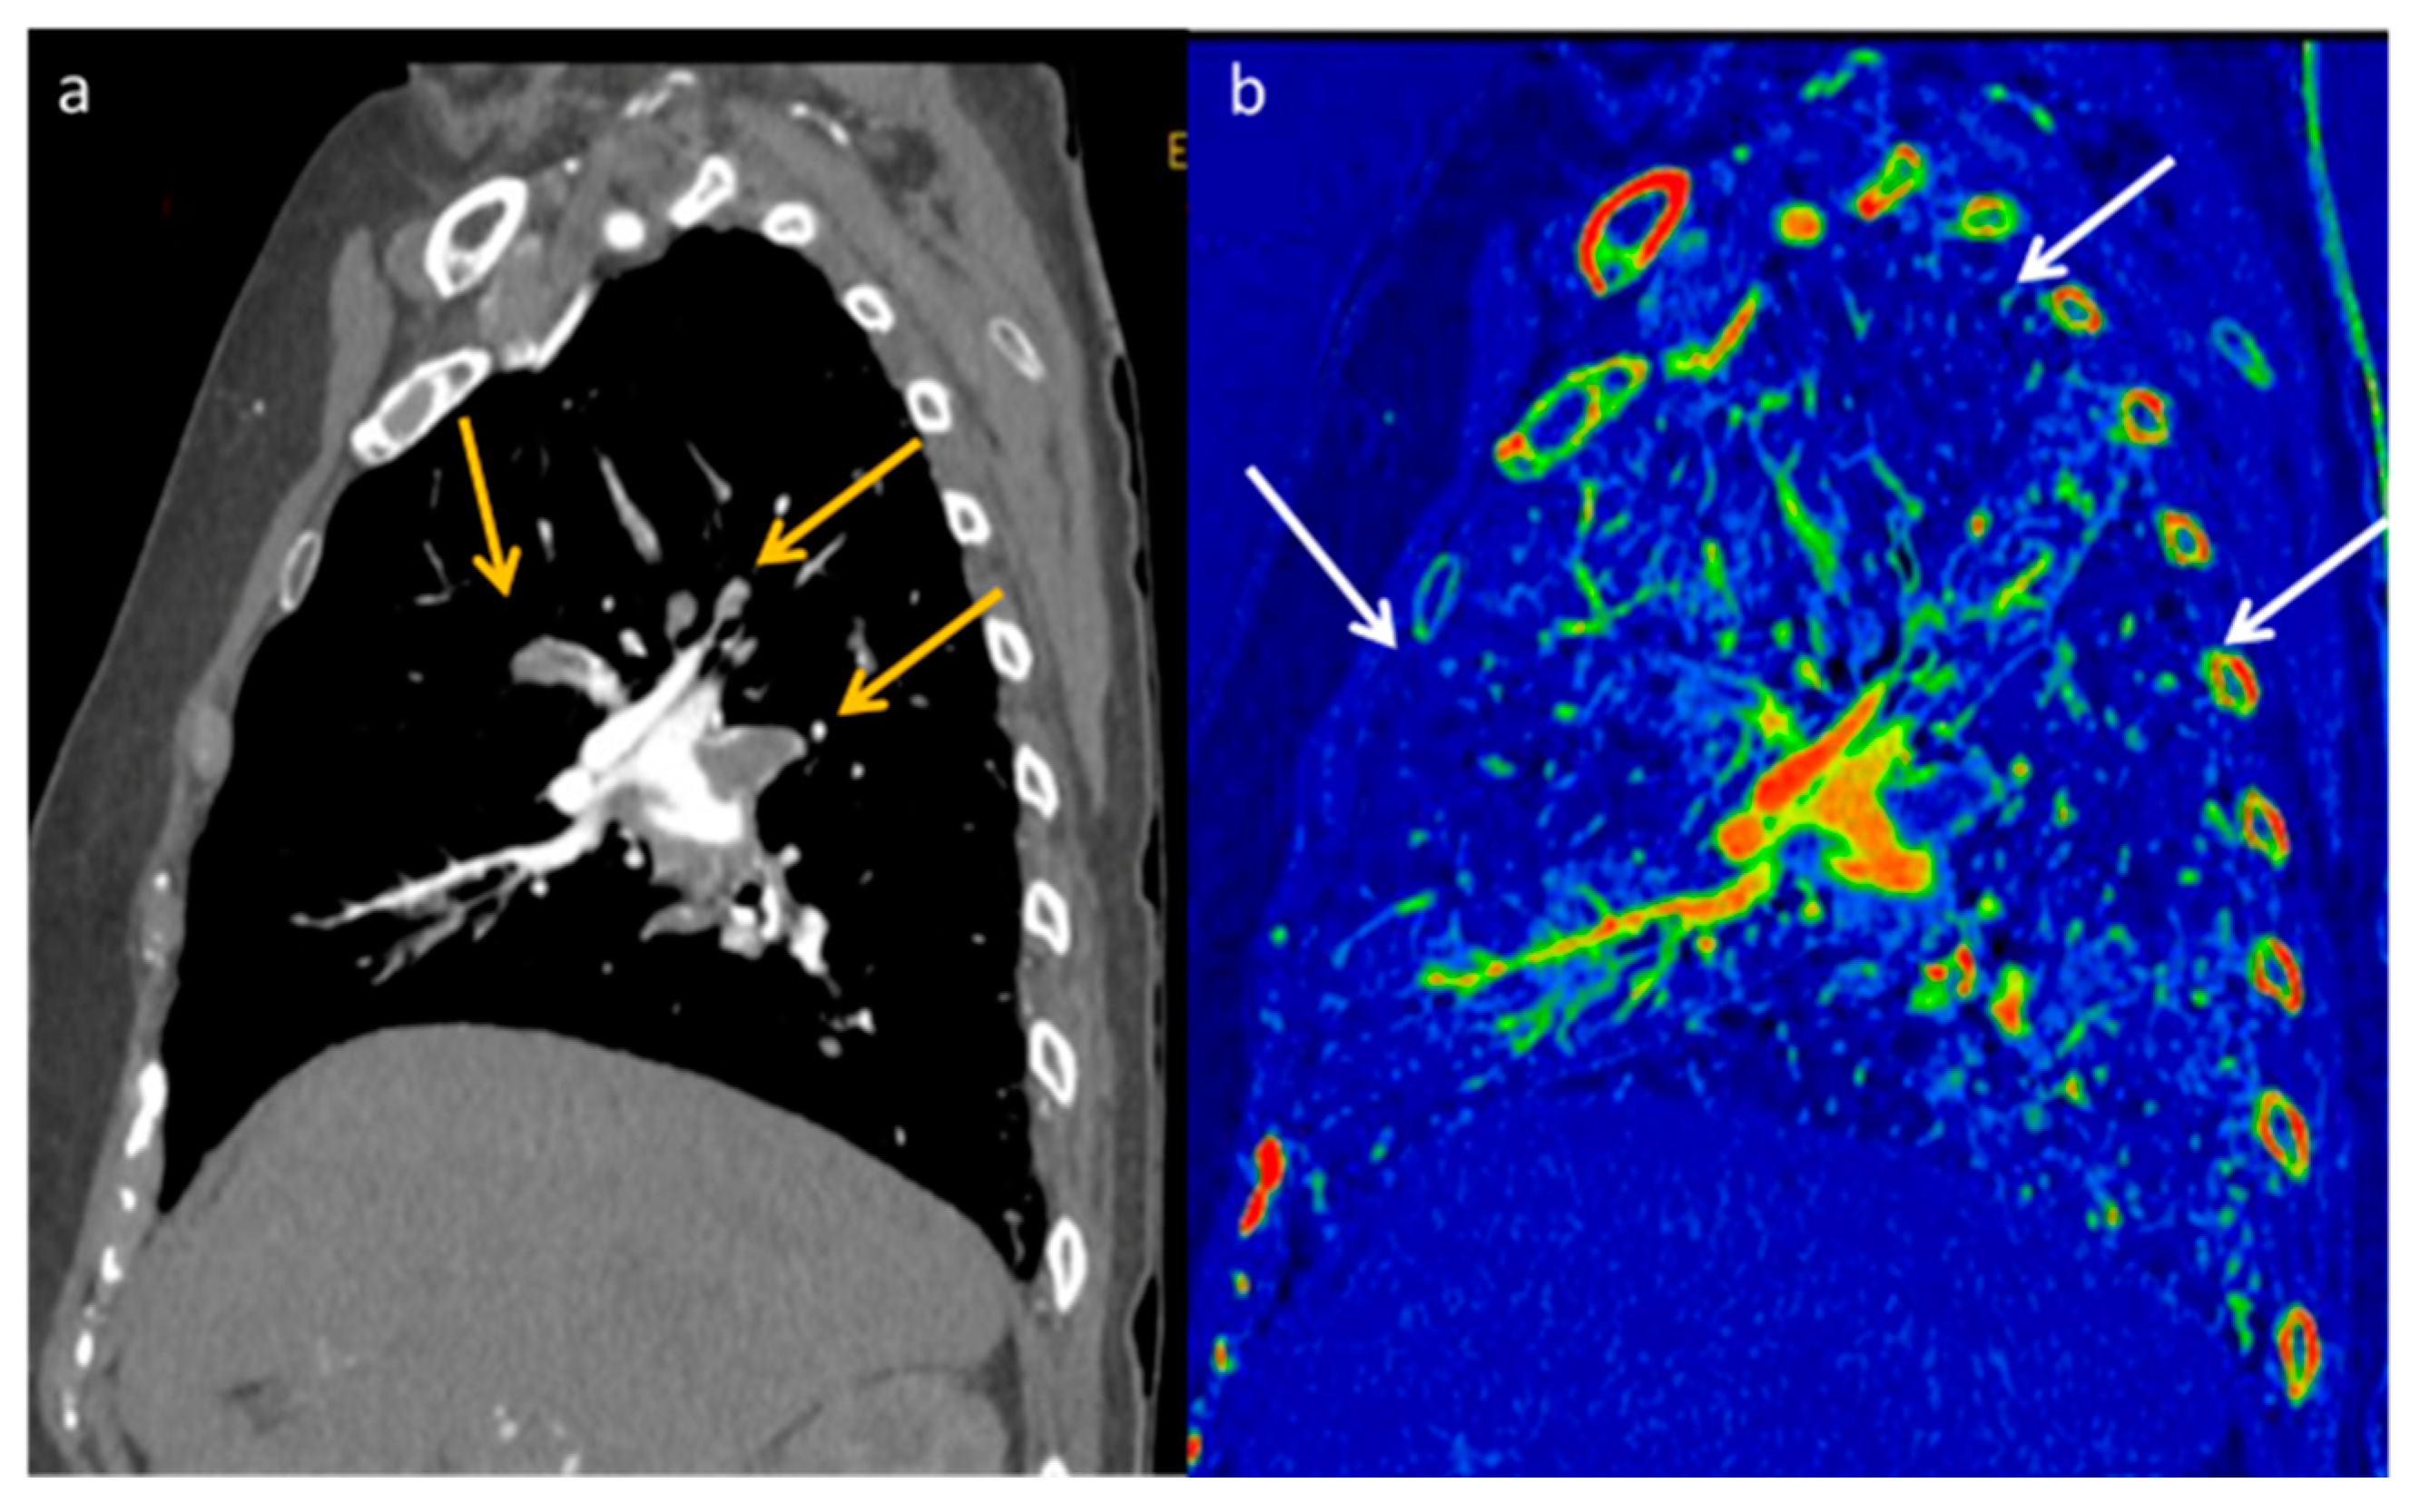

- Vlahos, I.; Jacobsen, M.C.; Godoy, M.C.; Stefanidis, K.; Layman, R.R. Dual-energy CT in pulmonary vascular disease. Br. J. Radiol. 2022, 95, 20210699. [Google Scholar] [CrossRef]

- Rajiah, P.; Tanabe, Y.; Partovi, S.; Moore, A. State of the art: Utility of multi-energy CT in the evaluation of pulmonary vasculature. Int. J. Cardiovasc. Imaging 2019, 35, 1509–1524. [Google Scholar] [CrossRef]

- Lefebvre, B.; Kyheng, M.; Giordano, J.; Lamblin, N.; de Groote, P.; Fertin, M.; Delobelle, M.; Perez, T.; Faivre, J.-B.; Remy, J.; et al. Dual-energy CT lung perfusion characteristics in pulmonary arterial hypertension (PAH) and pulmonary veno-occlusive disease and/or pulmonary capillary hemangiomatosis (PVOD/PCH): Preliminary experience in 63 patients. Eur. Radiol. 2022, 32, 4574–4586. [Google Scholar] [CrossRef] [PubMed]

- Masy, M.; Giordano, J.; Petyt, G.; Hossein-Foucher, C.; Duhamel, A.; Kyheng, M.; De Groote, P.; Fertin, M.; Lamblin, N.; Bervar, J.-F.; et al. Dual-energy CT (DECT) lung perfusion in pulmonary hypertension: Concordance rate with V/Q scintigraphy in diagnosing chronic thromboembolic pulmonary hypertension (CTEPH). Eur. Radiol. 2018, 28, 5100–5110. [Google Scholar] [CrossRef] [PubMed]

- Perez-Johnston, R.; Plodkowski, A.J.; Halpenny, D.F.; Hayes, S.A.; Capanu, M.; Araujo-Filho, J.A.B.; Weinsaft, J.W.; Ginsberg, M.S. Perfusion defects on dual-energy CTA in patients with suspected pulmonary embolism correlate with right heart strain and lower survival. Eur. Radiol. 2021, 31, 2013–2021. [Google Scholar] [CrossRef] [PubMed]